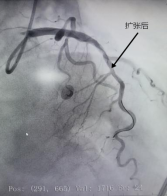

一位91岁高龄的老人,因四个多月来反复出现胸痛、心慌,最近一周症状再次加重,并伴有明显的食欲减退、吃不下饭,被送入pilipili 治疗。造影显示LCX(回旋支)远段狭窄90%,OM2开口及近段狭窄40%,随时有急性心梗的风险。李绍波主任运用IVUS(血管内超声)技术对病变血管进行检查,从传统“造影看轮廓”升级为“超声看结构”,清晰发现患者狭窄处病变以纤维斑块为主,且病变范围相对局限,符合药物球囊治疗指征。随后,李绍波主任为患者实施IVUS指导下的药物球囊治疗,术后患者血管恢复通畅,胸痛症状即刻缓解,同样无需植入支架。